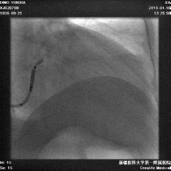

冠状静脉造影

● 通过长鞘造影,先冒烟,确认无夹层,造影后发现侧静脉分支,但不清楚远端情况。